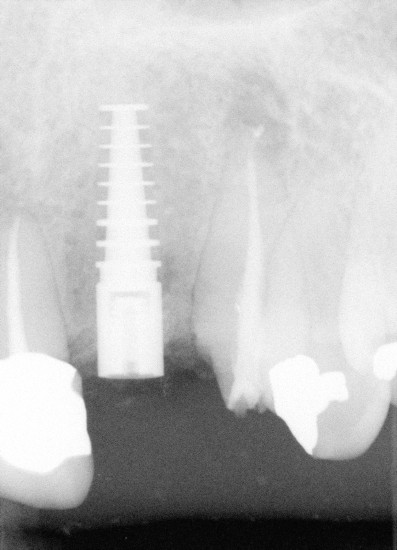

PA is taken immediately after D1 short implant (4x16 mm) is placed, back to main article